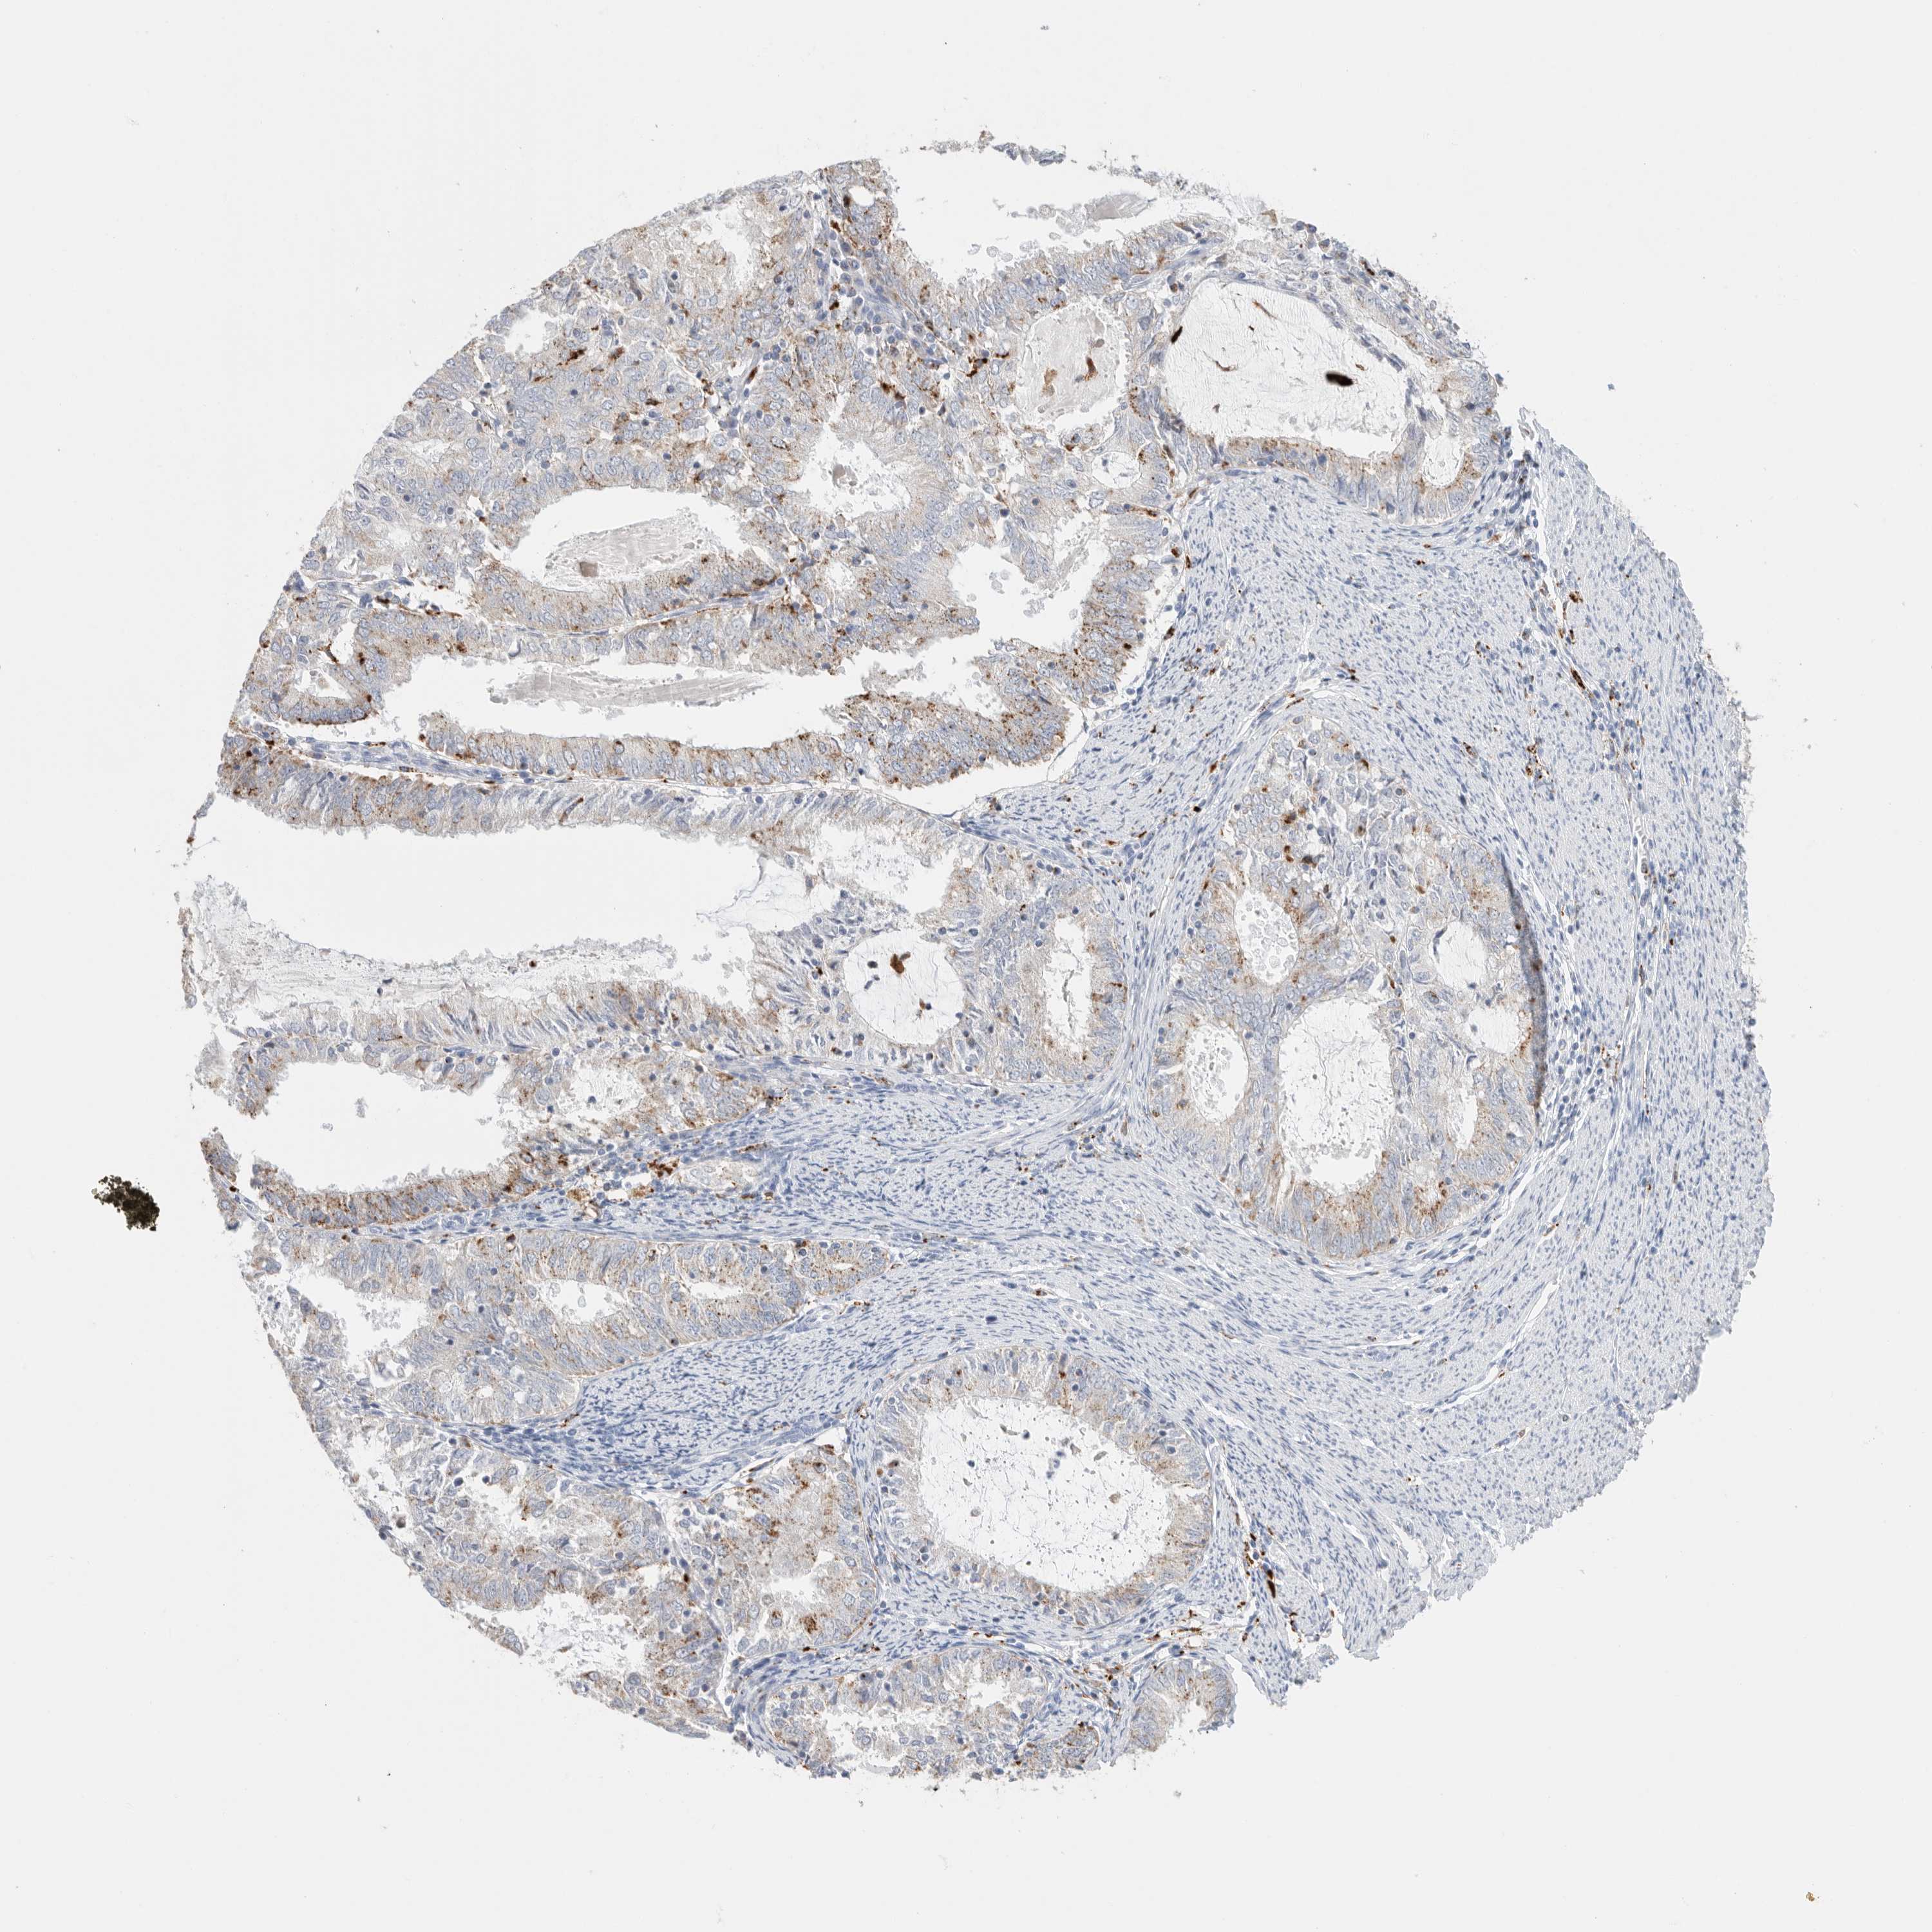

ENDOMETRIAL CANCER - Protein expressioni

A mouse-over function shows sample information and annotation data. Click on an image to view it in a full screen mode. Samples can be filtered based on level of antibody staining by selecting one or several of the following categories: high, medium, low and not detected. The assay and annotation is described here.

Note that samples used for immunohistochemistry by the Human Protein Atlas do not correspond to samples in the TCGA dataset.

Antibody stainingi

Antibody staining in the annotated cell types in the current human tissue is reported as not detected, low, medium, or high, based on conventional immunohistochemistry profiling in selected tissues. This score is based on the combination of the staining intensity and fraction of stained cells.

Each image is clickable and will lead to virtual microscopy that enables deeper exploration of all samples and also displays staining intensity scores, fraction scores and subcellular localization as well as patient and tissue information for each sample.

Antibody HPA025226

Antibody CAB019296

Staining

High

Medium

Low

Not detected

Intensity

Strong

Moderate

Weak

Negative

Quantity

>75%

75%-25%

<25%

None

Location

Nuclear

Cytoplasmic/membranous

Cytoplasmic/membranous,nuclear

Adenocarcinoma, NOS

Adenocarcinoma, metastatic, NOS